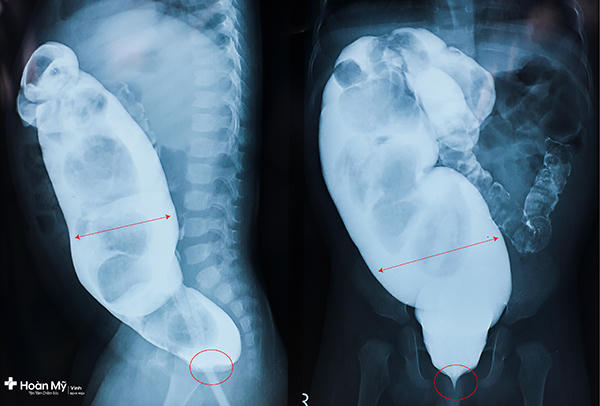

Gia đình đã đưa bé đến thăm khám và chữa bệnh, các bác sĩ phát hiện bé có 1 lỗ nhỏ ở trung tâm hậu môn. Thực hiện siêu âm bụng, chụp X – Quang, chụp cộng hưởng từ (MRI) thấy trực tràng và một phần đại tràng sigma giãn to do chất thải không được đẩy ra hết. Bác sĩ chẩn đoán bé bị hẹp hậu môn (2R ~ 3mm).